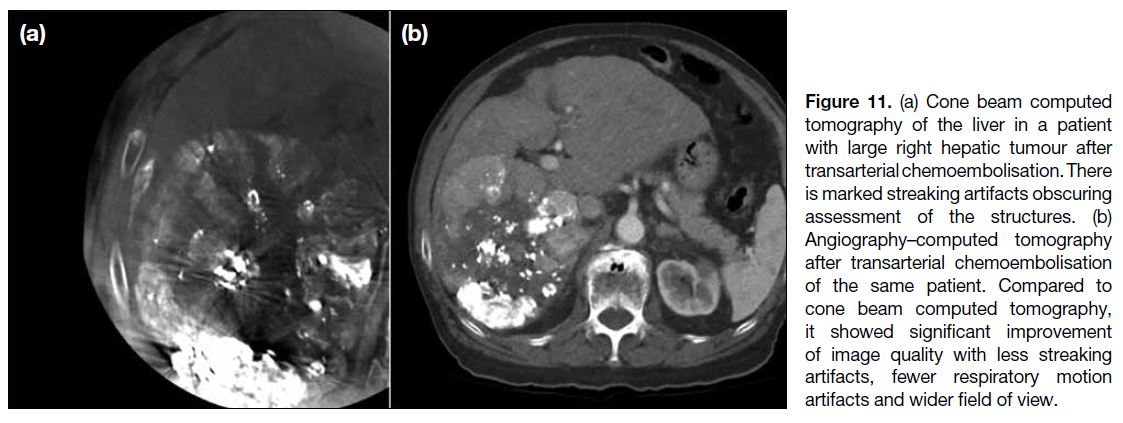

The above cases highlight the applications and

advantages of using the angio-CT system in various

IR procedures. Compared to CBCT previously used in

our unit, the image quality of CT hepatic angiogram in

angio-CT surpasses CBCT in visualisation of tumour,

identification of tumour arterial feeders, reduction of

streaking artefacts, wider field of view including the whole liver, fewer respiratory motion artefacts, and

higher overall subjective image quality[2] (Figure 11). It

also allows immediate postprocedural imaging to assess

treatment response, such as immediate lipiodol uptake

and presence of residual lesions, which are limited by

streaking and respiratory artefacts in CBCT.

Figure 11. (a) Cone beam computed

tomography of the liver in a patient

with large right hepatic tumour after

transarterial chemoembolisation. There

is marked streaking artifacts obscuring

assessment of the structures. (b)

Angiography–computed tomography

after transarterial chemoembolisation

of the same patient. Compared to

cone beam computed tomography,

it showed significant improvement

of image quality with less streaking

artifacts, fewer respiratory motion

artifacts and wider field of view.